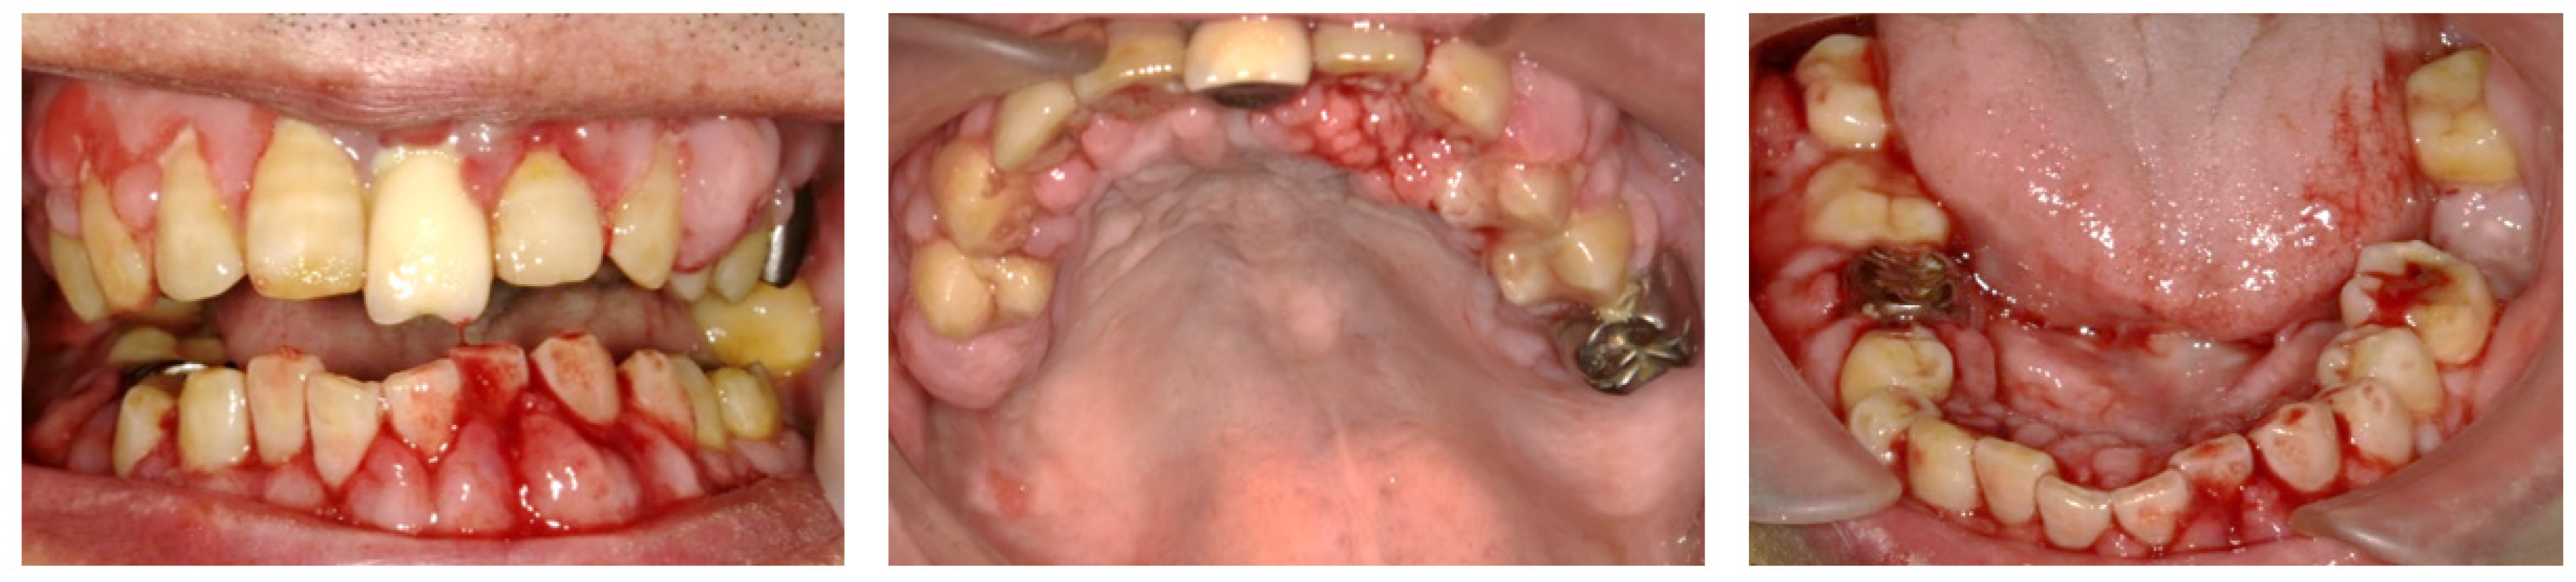

The acute symptoms resolved on day 7 (Figure 2A). We conducted a periodontal examination, including an assessment of probing pocket depth (PPD) and bleeding on probing (BOP). Because our patient had difficulty undergoing extensive examinations, we evaluated the one-point PPD instead of the six-point PPD (Figure 2B). Panoramic radiography was also performed (Figure 2C). During the periodontal examination, the entire circumference of each tooth was explored using the walking probe technique, and the value of the deepest pocket was recorded as representative of that tooth. In 11 teeth, PPD ≥ 4 mm with bleeding was detected. Of these, seven had deep pockets of >6 mm (Figure 2B). Panoramic radiography revealed a horizontal absorption of the entire alveolar bone (Figure 2C). On the basis of these comprehensive findings, NP was confirmed as the final diagnosis. Our patient also met the transiently and moderately compromised status criteria in the 2018 classification of NPD.

Figure 2.

The findings at 7 days after the first visit. (A) These intraoral photos show that the acute symptoms, including redness, swelling, and bleeding, have decreased. (B) Periodontal assessment includes tooth mobility (Mobility), bleeding of probing (BOP), and probing pocket depth (PPD) (maximum value on each tooth). Black color boxes indicate missing teeth. The green color box indicates acceptable PPD (not exceeding 3 mm). Yellow color boxes indicate PPD of 4 or 5 mm. Orange color boxes indicate PPD equal to or greater than 6 mm. BOP (−) indicates no bleeding. BOP (+) indicates bleeding. (C) Panoramic X-ray reveals that the entire alveolar bone has horizontal absorption.